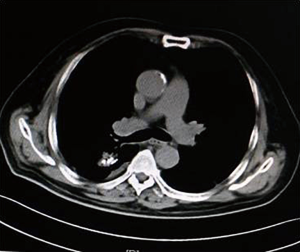

As illustrated in Table 3, tumors were significantly reduced in all 6 patients after the implantation of radioactive particles. A typical case can be seen in Figures 4,5.

As shown in Figure 7 and Figure 3, there were 2 CRs and 4 PRs after follow-up for 1 month, indicating a response rate (RR) of 6/6, and a disease control rate (DCR) of 6/6; six patients were followed up for 6 months, including one patient who refused follow-up visit (still alive),while the other 5 patients were followed up regularly, including 3 CRs and 2 PRs; five patients were followed up for 12 months, including 3 CRs, 1 PR and 1 PD, indicating an RR of 4/5, a DCR of 4/5, and a progression rate of 1/5; four patients were followed up for 18 months, including 3 CRs and 1 SD, indicating a RR of 3/4 and a DCR of 4/4; four patients were followed up for 24 months, including 1 patient who refused a follow-up visit (still alive), while the other 3 patients were still followed up regularly; there were still 4 patients who were followed up for 30 months, including 1 patient who refused follow-up visit (alive) and 3 patients who were followed up on a regular basis; one patient was followed up for 36 months and had a recurrence of primary lesion, with the response being evaluated as PD. In addition, Figure 7 shows that patient E achieved significant response after implantation of 125I particles, and the response was evaluated as CR 1 month after implantation (Figures 8,9); however, the primary lesion recurred and was enlarged with left lung metastasis in month 12 (Figures 10,11), whereupon the response was evaluated as PD. The patient was given CT-guided implantation of 125I radioactive particles again for treatment of the recurrent lesion. The repeated pulmonary CT after re-implantation showed significant reduction of tumor (reduction rate 27.32%), as shown in Figure 12, and the response was subsequently re-evaluated as SD.

Other relevant studies have shown a unique advantage of implantation of radioactive particles in the treatment of lung cancer. In a study by Lu et al. (10), 15 patients with obstructive pneumonia caused by central type lung cancer were given a bronchoscopic implantation of 125I radioactive particles, and followed up in months 2, 6, 12, 18 and 24 after implantation. The median survival was 15.6 months, and the one-year lung recruitment rate was 80.0%, which significantly improved the quality of life. To compare, in our study’s response evaluation from regular follow-up of patients who received the CT-guided implantation of radioactive 125I, it was found that the tumors had significantly shrunk in all 6 patients. Typical cases are illustrated in Figures 4 and 5, and as can be seen in Figure 6, the most obvious reduction of tumor was seen in the 6th month of follow-up. In the 5 patients who were followed up, there were 3 CRs, indicating an RR of 5/5 (100%) and a DCR of 5/5 (100%). This shows that the implantation of radioactive particle achieved the best response within 6 months in the treatment of early lung cancer. In addition, as Figure 3 shows, 5 patients were followed up 1 year after implantation and had a survival rate of 5/5 (100%), 4 patients were followed up 2 years after implantation and had a survival rate of 4/4 (100%), and the longest time after enrollment was up to 3 years and 5 months; at the time of writing, this patient is still alive. The observations above demonstrate the significant efficacy of the implantation of 125I radioactive particles in treatment of early lung cancer.